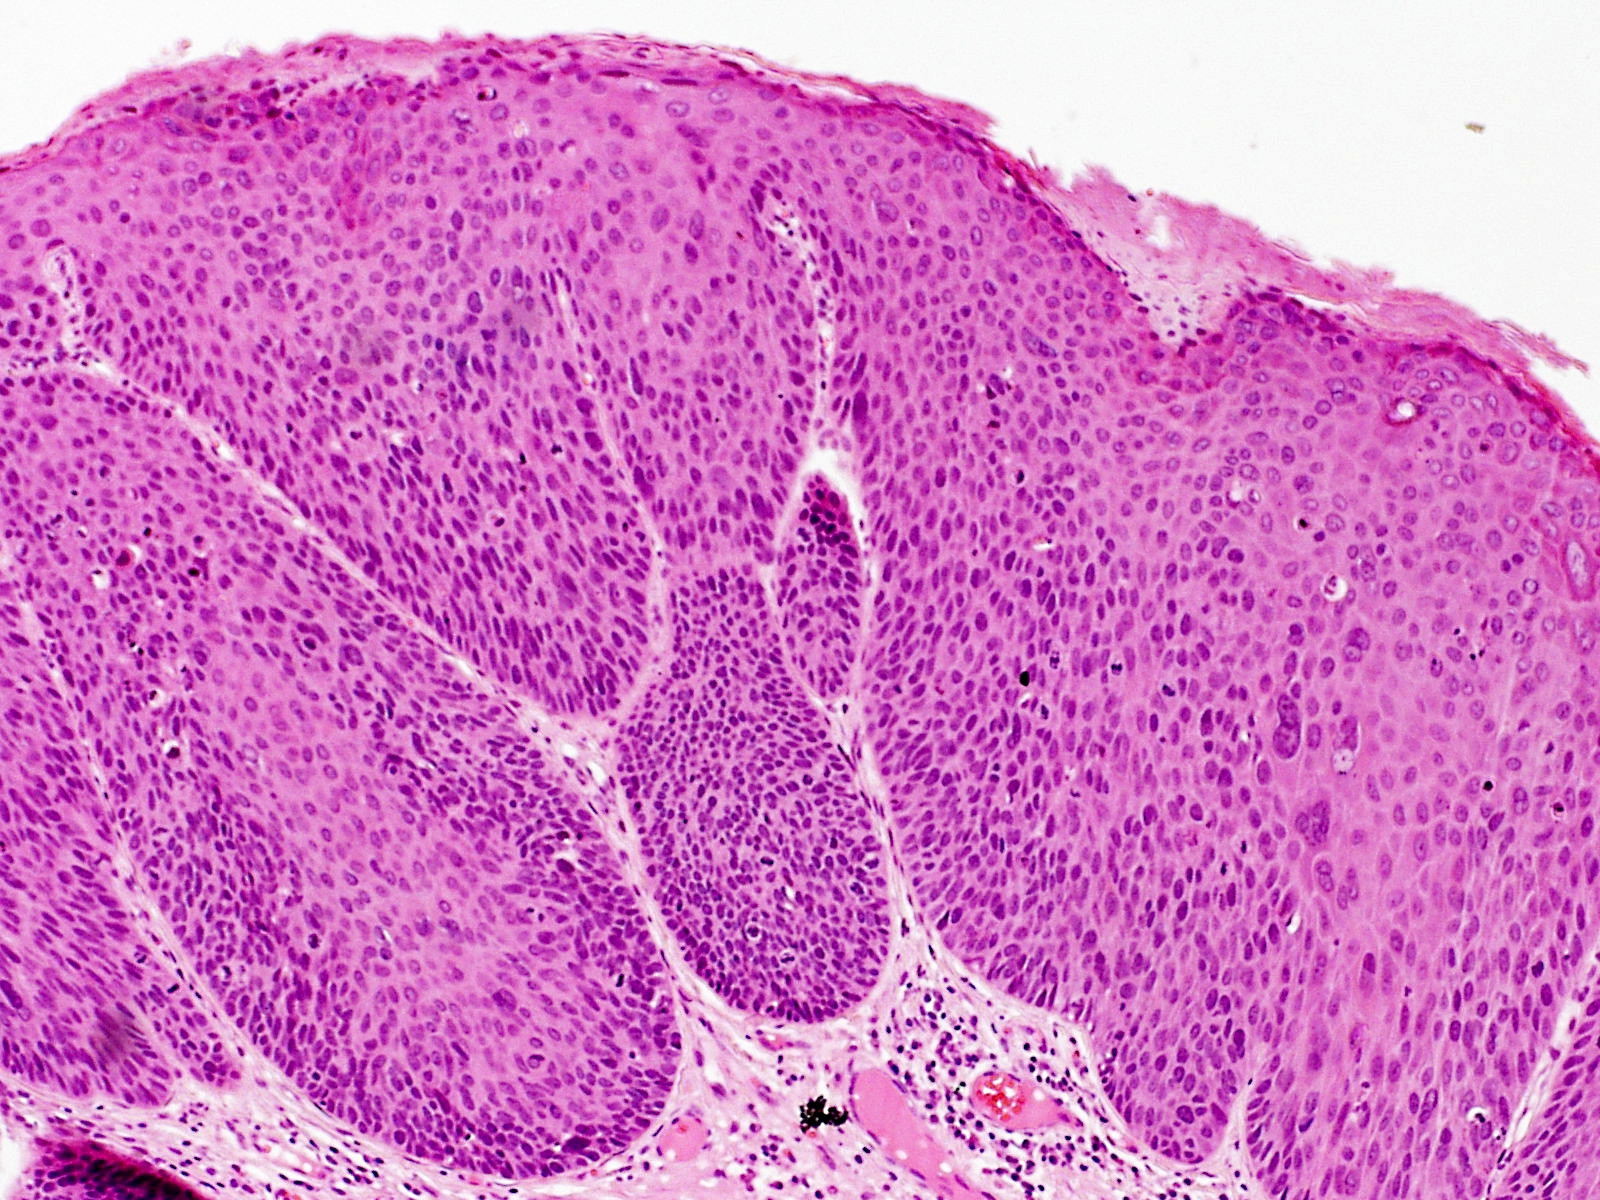

Bowenoïde papulosis (Bowenoid papulosis) kan worden

beschouwd als een overgangsvorm tussen een condyloma acuminata en morbus Bowen

(intraepitheliaal carcinoom). Een nieuwere term voor dit soort laesies is

intraepidermale

neoplasie (

AIN1,

AIN2,

AIN3, PIN, VIN, CIN). Klinisch zijn er multipele huidkleurige,